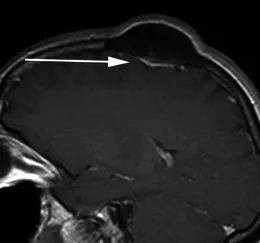

案例五:49岁女性患者,因头皮肿块就诊。矢状位增强T1加权序列显示左侧顶骨明显骨质增生,病灶主体向颅外突出。邻近骨性病变下方可见薄片状、均匀强化轴外软组织影(箭头),符合扁平型脑膜瘤影像特征,经手术病理证实。